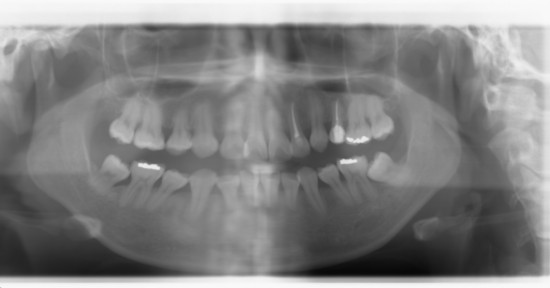

교정을 하다가 중간에 군대를 가는바람에 브라켓을 떼고 5년만에 재교정 하는건데요... 일단 제가 상악이 센터가 2.5mm정도가 틀어진상태구요. 사진 보시면 앞니 바로 왼쪽치아(2번치아)가 뿌리부분이 살짝 안쪽에 자...

발치질문드려요~

안녕하세요 26살 성인 남성입니다. 재교정은 보통 유지장치 사용소홀로 인해 치아가 다시 되돌아와서 하곤하는데 저같은 경우는 군입대의 사유로 도중에 브라켓을 떼어버렸습니다. 제가 19살9월에 양쪽 4번치아 위아...

안녕하세요 선생님 중학생때 치과기술이 그닥 좋지 않은 외국에서 교정을 했는데 제대로 교정이 되지 않았어요. 사랑니 이런걸 감안하지도 않고 끝나고 엑스레이도 찍어보지 않더군요. 어처구니가 없긴하지만 그땐 말...